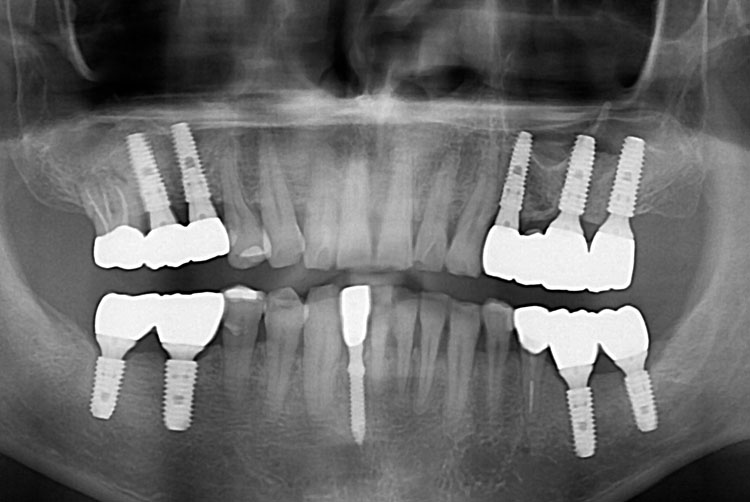

[임플란트] 임플란트

치료후 : 2017-09-28

세종치과는 많은 환자와 다양한 케이스를 바탕으로 항상 편안한 임플란트 수술을 제공하고자 노력하고,

오래동안 튼튼히 쓸 수 있는 임플란트 수술을 가장 큰 목표로 삼고 있습니다.